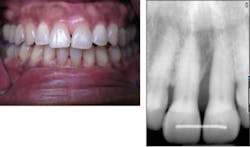

Case No. 3 — Mr. First Time

A 79-year-old African American male was diagnosed with chronic periodontitis. He had no prior dental care and presented with full dentition, no caries, and advanced bone loss with tooth mobility in molar areas. His chief complaint was a loose upper right tooth. The LANAP protocol was performed over two appointments with local anesthetic. Treatment was done in August 2012.

Mr. First Time before the LANAP protocol.

Mr. First Time is very pleased with his care despite his initial trepidation. Tooth mobility has lessened, and sensitivity is minimal despite the significant amount of calculus removal that was done and the resulting root exposure. The tooth with +3 mobility was removed. The patient realizes other teeth may need extraction, but at this time no additional extractions are planned. (November 2012)

Mr. First Time after treatment.